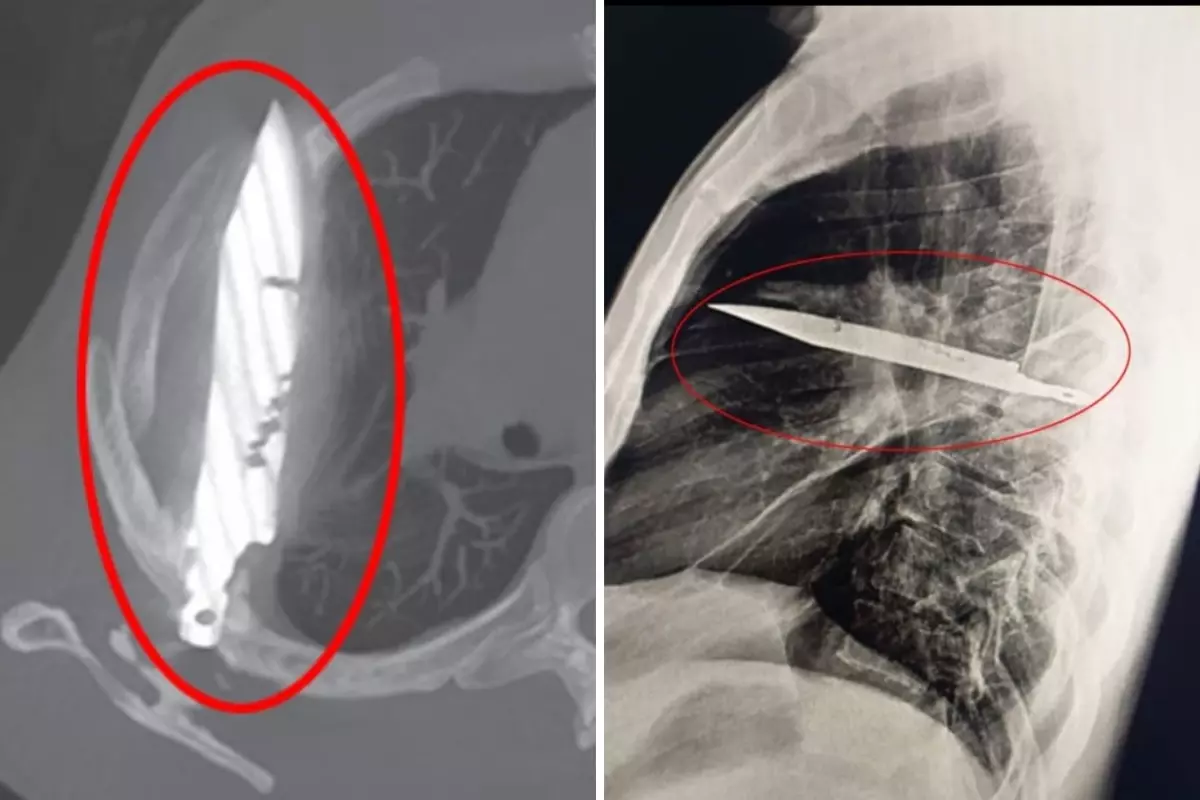

Röntgen sonucunda, adamın göğsünde 8 yıldır saplı duran bir bıçak olduğu ortaya çıktı. Hasta, yıllar önce yaşadığı kavgada yaralandığını ve o günden beri sağlık sorunu yaşamadığını belirtti. Vietnam'da ise bir başka şaşırtıcı olay yaşandı.

Tanzanya'da 44 yaşındaki bir adam, sağ memesinin altından iltihap akması şikâyetiyle hastaneye gitti. Doktorlar ilk muayenede herhangi bir ağrı, nefes darlığı, öksürük ya da ateş bulgusuna rastlamadı. Ancak yapılan röntgen, herkesin ağzını açık bıraktı: Adamın göğsünde tam sekiz yıldır saplı duran bir bıçak vardı.Hasta, yıllar önce yaşadığı şiddetli bir kavga sırasında yüzünden, sırtından, göğsünden ve karnından yaralandığını, o zaman tedavi gördüğünü söyledi. O günden beri ciddi bir sağlık sorunu yaşamamıştı. Fakat son günlerde fark ettiği iltihap nedeniyle doktora başvurunca, yıllardır göğsünde "unutulmuş" bıçak ortaya çıktı.

Bıçak, sağ kürek kemiğinden girip hayati organlara zarar vermeden göğüste kalmıştı. Ameliyatla çıkarılan bıçakla birlikte ölü doku temizlendi. Hasta yoğun bakımda bir gün, normal serviste ise 10 gün kaldı. Doktorlar, takip kontrollerinde hastanın tamamen iyileştiğini duyurdu.Vietnam'da ise akıllara durgunluk veren başka bir olay yaşandı.Hanoi'de bir adam, makatından giren 66 santimetrelik yılan balığının bağırsak duvarını kemirmeye başlamasıyla dayanılmaz ağrılar yaşadı. Çekilen röntgende balığın bağırsaktan çıkmaya çalıştığı görüldü.Doktorlar önce balığı özel bir cihazla çıkarmaya çalıştı, ancak önünde tıkalı bir limon buldular. Ameliyatla karnı açılan adamdan balık pense yardımıyla çıkarıldı. Ardından limon da anüsten geri itilerek çıkarıldı. Bağırsaktaki delik dikildi ve sızan dışkı temizlendi.